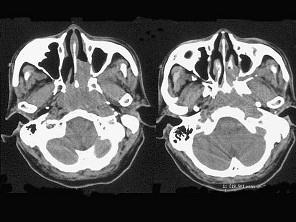

问题 男,64岁,间断性流鼻血一年余,近1个月加重,CT如图所示,最可能的诊断为 ( )

选项 A、鼻咽部淋巴组织增生 B、鼻咽癌 C、鼻咽纤维血管瘤 D、鼻咽部恶性淋巴瘤 E、鼻咽部腺样体增生

答案 B